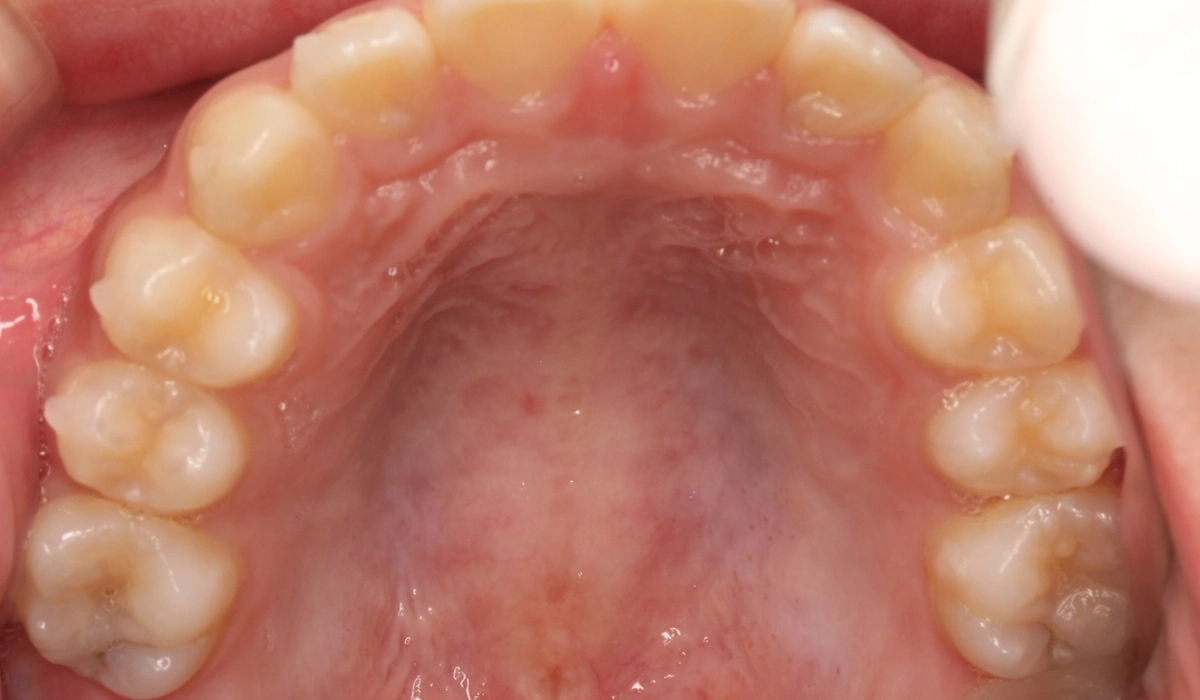

術前:上顎

術後:上顎